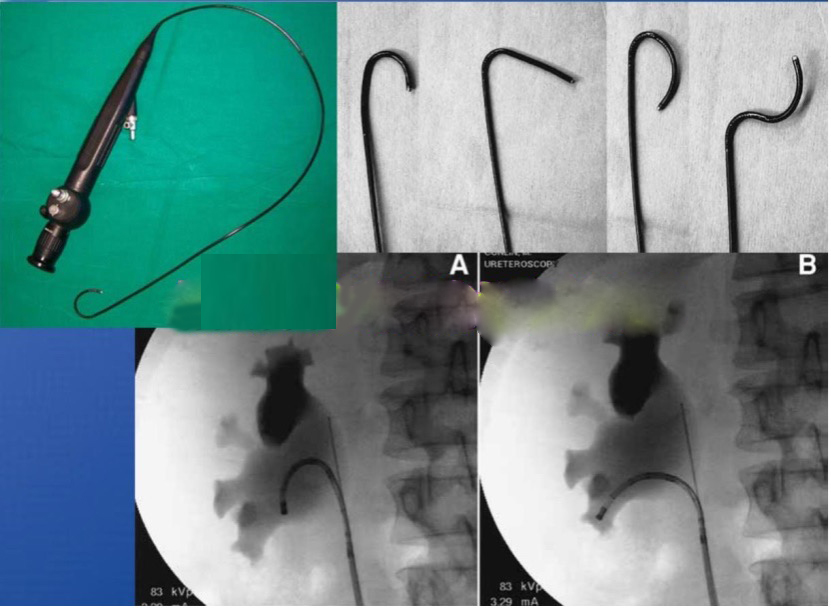

对于小于2-75px的肾结石患者,或者输尿管上段结石采用硬镜无法窥及或者结石上移的患者,则需要在可弯的输尿管软镜下进行碎石手术。该技术同输尿管硬镜手术一样,无需手术切口,恢复快,创伤非常小。本院在福州市内较早引进负压吸引和智能控压设备,确保手术在肾盂内低压状态下完成,同时缩短了手术时间,进而增加了手术的安全性,同时可以将碎石清除率大幅提高。